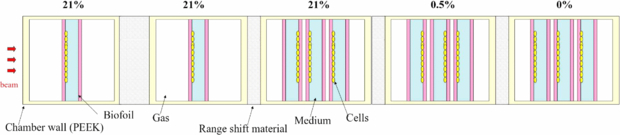

Dedicated plans were produced for several beamtimes performed at GSI in order to test the predictive features of the code and the reliability of the semi-empirical OER model used. Given the small impact of the LET induced OER reduction for an extended irradiation with carbon, as explained above, the aim of the experiment was also to analyze if this effect on the survival would be detectable through biological dosimetry, and if yes, whether the proposed simplified model would be consistent for describing the affected region. For that, a specifically designed exposure chamber with conditioned oxygenation has been used, which has been developed and patented at GSI (Schicker et al 2009). CHO-K1 cell lines were grown on a 4.5 cm2 area on gas permeable foil supported on a PVC-ring. Each ring is covered with a 3 mm layer of medium and sealed with a second foil. This allowed to gas the chamber for several hours with standard gas mixtures: 95% N2, 5% CO2 for anoxic condition and 94.5% N2, 5% CO2, 0.5% O2 for hypoxic condition. The ring can be turned in the two opposite orientations with respect to the beam, allowing to expose the cell layer at different depth positions. The chambers are made of polyether etherketone and available either in a simple shape, containing a single ring, or with three rings (details in Tinganelli et al (2013)). The chamber's wall for the beam entrance has a thickness of 1 mm and the gas flow was measured with a thermal mass flow meter calibrated for nitrogen.

In a first beamtime, a tumor tissue with three different concentrations of oxygen has been simulated. A 4 cm water equivalent length target centered at 8.1 cm from the beam entrance was planned, divided in a first region (from the proximal end) of 13 mm of normoxia, a second layer of 13 mm of hypoxia (pO2 = 0.5%), and a last one of complete anoxia (pO2 = 0%), 14 mm, a phantom corresponding to that of figure 8, right. Three chambers, each one containing three rings and entirely gased at the corresponding concentration, were then placed in a corresponding position after accounting for the path length conversion factors. The oxygenation condition has been checked to be maintained during the time of irradiation, after performed tests on the concentration changes after interruption of the gasing procedure. Additionally, two normoxic single chambers were placed in the entrance channel as a further control (figure 11). The plan was prepared in order to have a 10% survival in the target in a normoxic case, but was later recomputed according to the average photon parameters obtained from all the measurements performed in our group in the last three years on these cells on film support: αx = 0.171 Gy−1, βx = 0.02 Gy−2, Dt = 17.5 Gy (Tinganelli et al 2013). In order to assure uniformity in the dose coverage, the target was chosen as a broad parallelepiped, with Δx = 6 cm and Δy = 10 cm. A single beam was used, with energies optimized by the program to cover the requested range (Emin = 173.63 MeV/u, Emax = 224.81 MeV/u). For having a reasonable fast irradiation we imposed a set of energies corresponding to depth steps of 3 mm, corresponding to the size of the ripple filter employed. For the lateral extension the raster spots were imposed at steps of 2 mm in both directions (x, y) and for each of them beam size was 5.4 mm FWHM.

Figure 11. Schematic top view of the irradiation configuration for the pilot experiment. On top, the oxygenation condition (pO2) induced inside the corresponding single or triple chamber. The cells are let grown on different edges of the ring, as shown, in order to cover different depth positions.